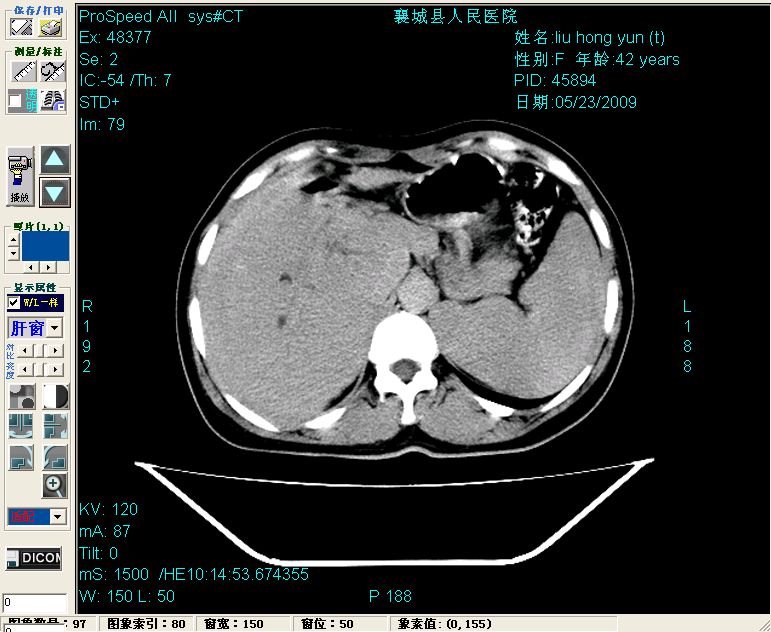

增强:

增强动脉期前述低密度区轻度早其强化,门脉期强化程度显著增高,延期扫描强化程度下降,但仍为相对高密度影

结合病史考虑,1现在引起黄疸体征的原因应该是胆总管胰段结石阻塞,建议局部胃肠造影剂排空后复查.

3脾大,可能与动门脉瘘所致门脉高压有关